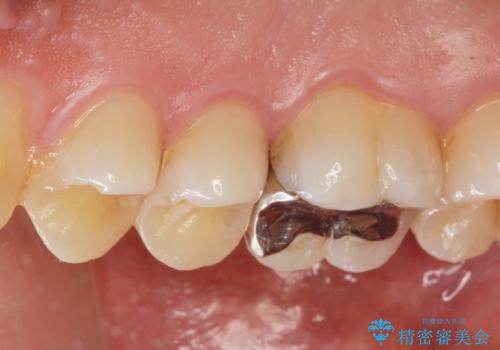

- 定期検診でレントゲンを撮影したところ虫歯があったので拡大鏡下で虫歯を取り除き、白い詰め物にて治療しました。

無事歯の神経を取らずに白い詰め物で治療する事ができました。